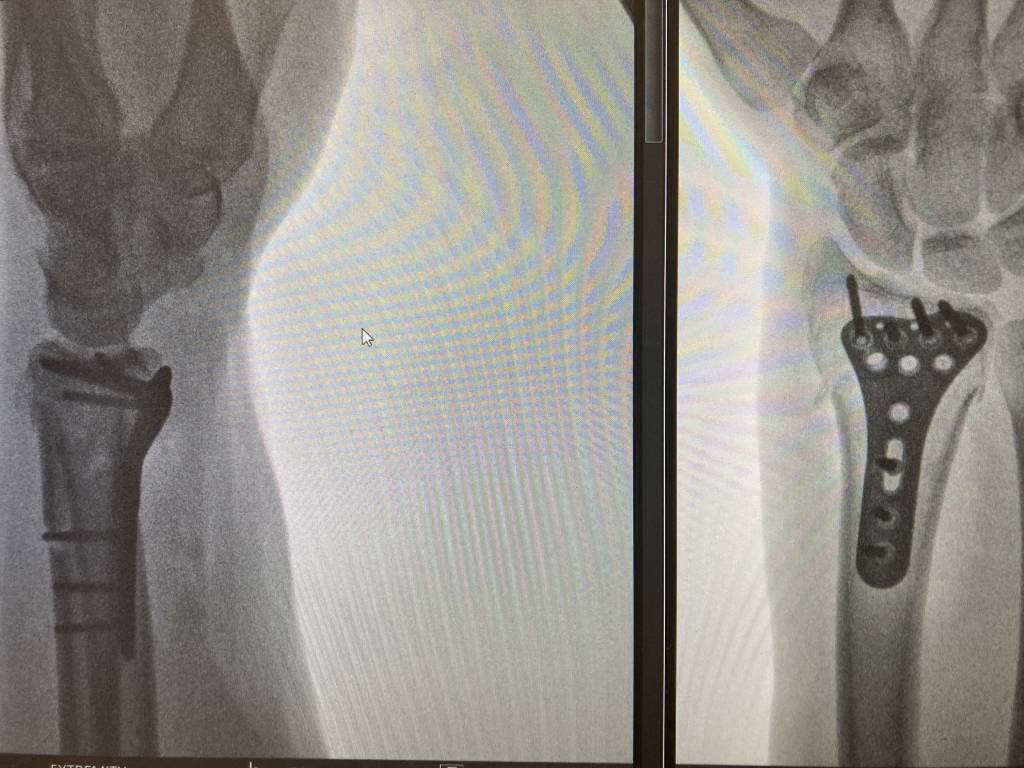

I've had a little fall and broken my radius, oops. The initial break was 30/05 and it was plated on 06/06, wound check and new cast on Friday. I'm pretty sure there will be a few people here that have done similar so please share recovery dos and don'ts.

Pics for context